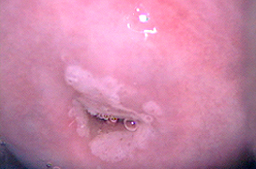

NIC 2 o Displasia moderada asociada a infección por VPH

Displasia leve con gran ectropión y lesiones por VPH en vulva.

Neoplasia Intraepitelial de Cérvix grado 2 o Displasia moderada.